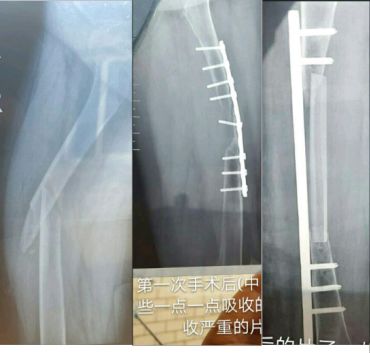

点评:骨折不愈合与手术手法手术中剥离关系比较大;与受伤时的暴力软组织损伤有关:与固定方法有关。骨折不愈合,钢板必然断(引用图)

开放骨折,软组织损伤严重,骨不连接导致钢板断裂。应当在伤口愈合后及时干预植骨

钢板断裂(骨不愈合)

钢板断裂后骨愈合(去除了应力遮挡)

愈合和内固定的失败是竞赛关系

钢板的断裂是弯曲力和扭力所致,螺钉的松动拔出是因为固定物松动,骨折不愈合导致锁定钢板的断裂依然符合此原则

剥离太多,术者手术中的预见性很重要,必要时要一期植骨。如果发生骨不愈合内固定迟早失败。同一肢体多处骨折有手术指征,方法技巧要提高。